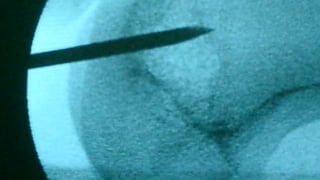

Distal Femur retrograde nailing

Brief steps of distal femoral retrograde nailing of femur